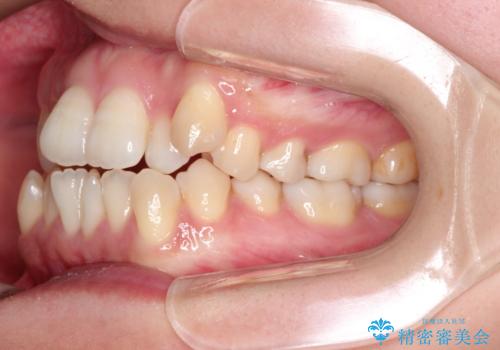

前歯の叢生があり、上下の前歯が接触していない開咬という状態でした。

左側の上下の前から4番目の歯を抜歯して、矯正することとしました。